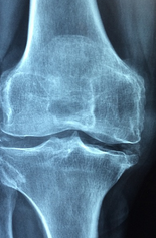

무릎 통증 원인에 대해 자세히 알아보도록 하겠습니다. 무릎 관절은 우리 몸의 중요한 부분으로, 우리의 움직임을 지원하고, 충격을 흡수하고, 균형을 유지하는 역할을 합니다. 하지만 무릎 관절은 나이가 들면서 퇴행성 관절염이라는 질환에 걸릴 가능성이 높아지는데요, 이는 관절의 연골이 마모되어 통증과 염증, 운동장애를 일으키는 병입니다.

- 관절염 : 무릎 관절에 염증이 생기는 질환입니다. 염증은 관절의 손상, 감염, 면역 반응 등에 의해 발생할 수 있습니다. 일반적으로 무릎 염증 증상은 다음과 같습니다. 무릎을 움직일 때 무릎뼈에서 소리가 난다, 비가 오는 날 무릎 통증이 심해진다, 무릎이 뻣뻣해서 움직일 때 불편하다, 무릎 부위가 붓는다, 무릎 관절이 약해서 걷거나 서있을 때 종종 무릎이 구부러짐.

골 관절염은 '퇴행성 관절염'으로 무릎에 영향을 미치는 가장 흔한 유형의 관절염이에요. 일반적으로 중년이나 노년층에게 많이 나타나지만 부상이 반복되거나 과체중과 같은 관절의 과도한 스트레스로 인해 발생할 수 있어요.